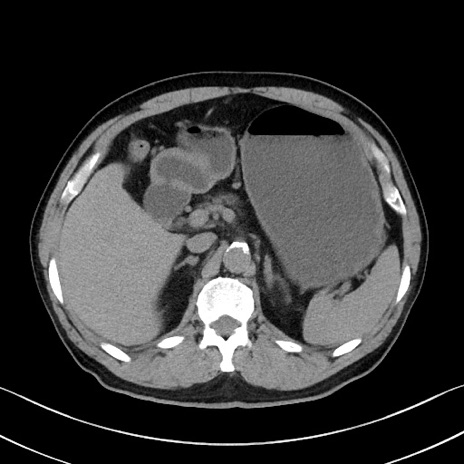

症例35(横断像)

【症例】70歳代 男性

【主訴】腹部膨満、嘔吐

【現病歴】昨日より腹部膨満感出現。本日増悪し、仙痛出現。嘔吐あり、受診。

【既往歴】糖尿病、胆摘後

【身体所見】BP 149/80mmHg、HR 74/min、BT 35.9℃、腹部:膨満、軟、圧痛なし。腸雑音減弱あり。上腹部正中切開瘢痕あり。

【データ】WBC 13500、CRP 1.72

冠状断像